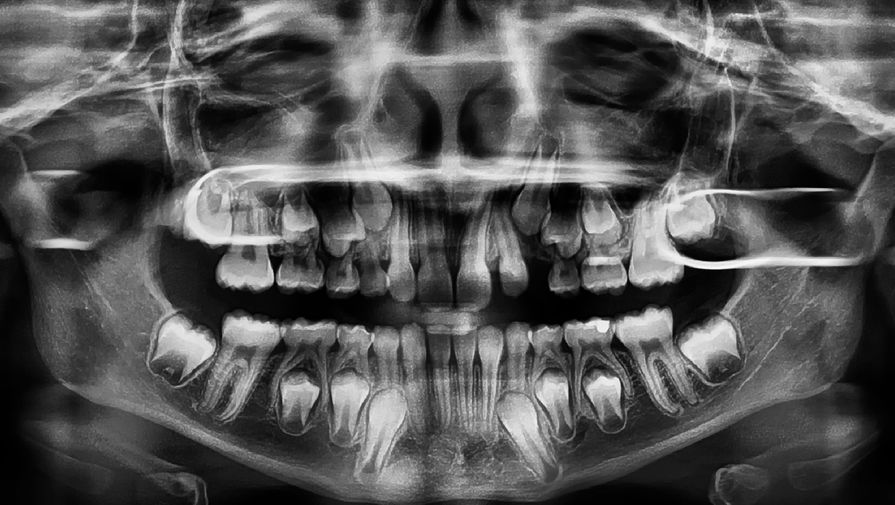

Корень и шейку зуба человека покрывает особая костная ткань — цемент. Она на треть состоит из органических веществ и служит для плотного закрепления зуба в зубной лунке. На протяжении жизни, почти как годовые кольца у деревьев, образуются новые слои цемента. Они и привлекли внимание ученых.

С помощью поляризационной световой микроскопии исследователи рассмотрели 47 зубов от 15 людей, которые жили в наше время, но уже умерли. Возраст людей составил 25-69 лет. От их родных ученые получили информацию об истории болезни каждого человека, образе его жизни, важных событиях — например, переезде из города в сельскую местность, и прочие данные.

Изучая слои цемента на зубах, ученые обнаружили заметные изменения микроструктуры, которые по времени появления совпадали с теми или иными важными жизненными изменениями.